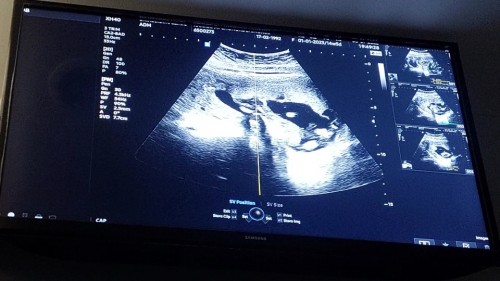

ขอดูตัวน้อยของแม่ไปทีมมกราคมหน่อยจ้า☺️☺️ อาการแม่ๆเป็นยังไงกันบ้างคะ บ้านนี้กินไม่ได้เลยกินนมก็ไม่ได้ออกทางเดิมตลอด🥺 #ทีมมกราคม 19 มกราคม 2566